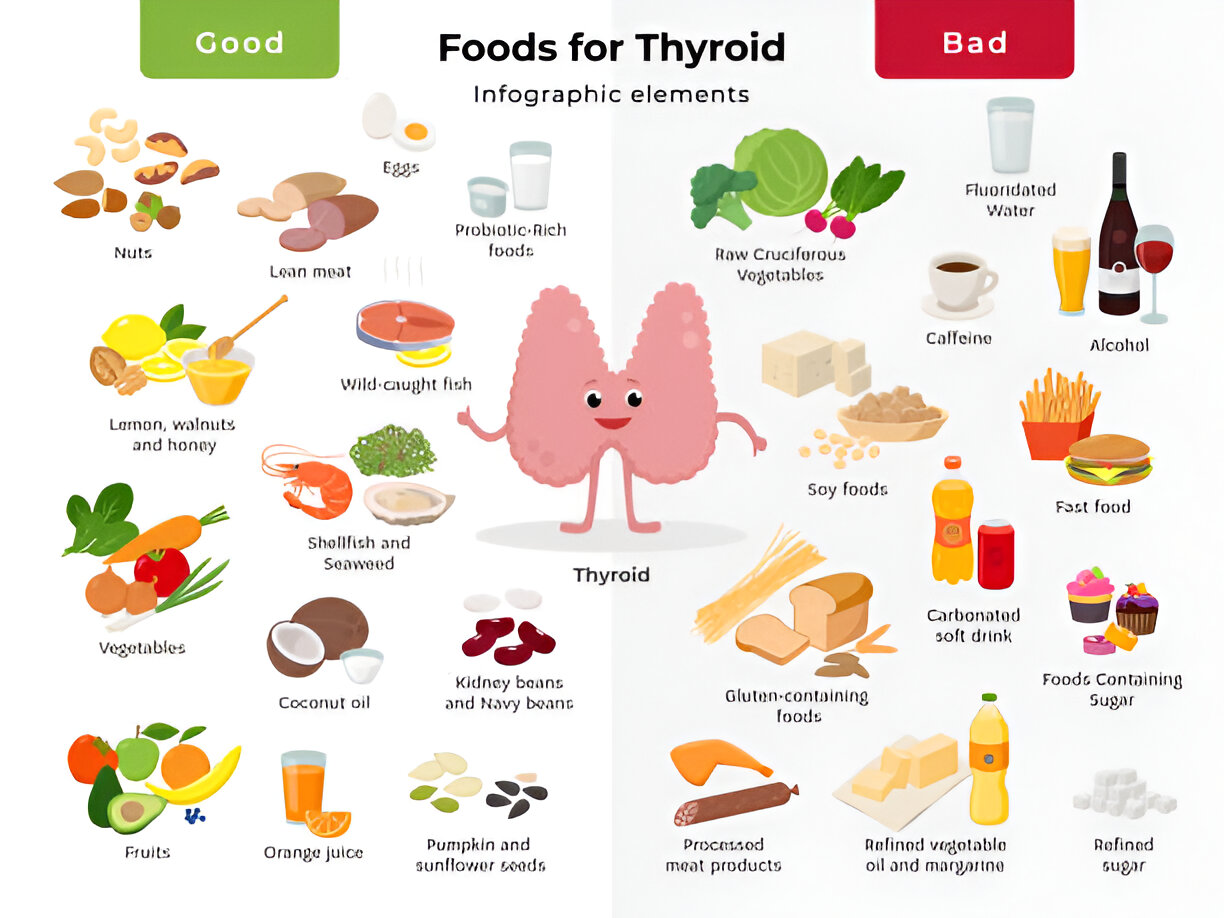

Thyroid gland is a small, butterfly shaped organ which is located at the base of the neck. The gland functions to produce hormones which regulates the important functions of the body. In this blog we will discuss the types, causes and symptoms of thyroid and thyroid disorders.

The thyroid gland is a butterfly-shaped gland which is located at the base of the neck and is responsible for producing hormones which regulate metabolism, energy levels and even mood. A thyroid nodule is a lump or growth which forms within the thyroid gland.

Thyroid disorders are among the most common endocrine issues worldwide, affecting millions of people, especially women. Whether it's hypothyroidism (underactive thyroid) or hyperthyroidism (overactive thyroid), these conditions can significantly impact your metabolism, energy levels, weight, and overall well-being.